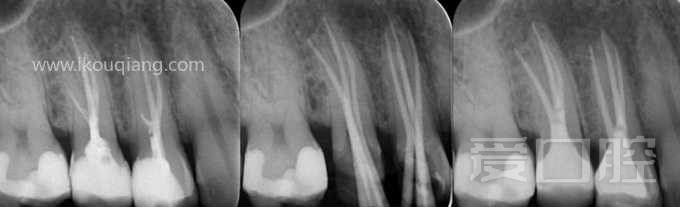

看个根充 —— 上4、上5 分别3条根管